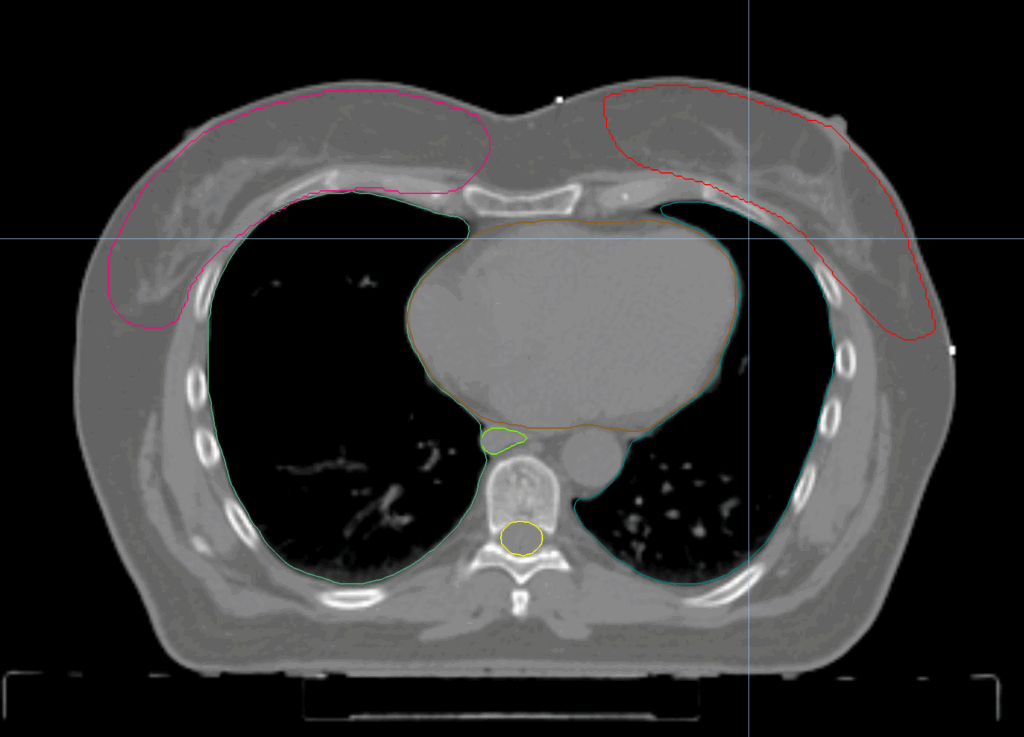

Planning CT Images

PTV(s) Volume, Length

1590 cc, 24 cm